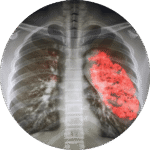

Akciğer enfeksiyonları (zatürre)